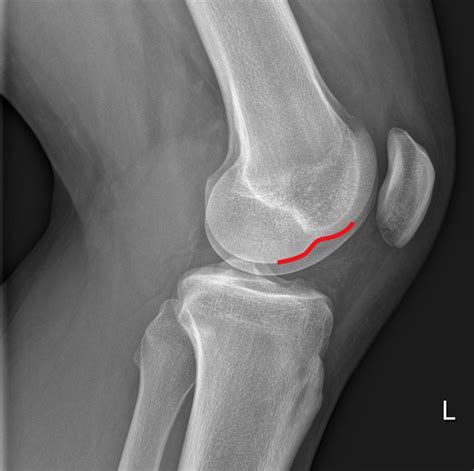

Osteochondral Lesions

An osteochondral lesion involves damage to the cartilage and the underlying bone. These can occur due to repetitive micro-trauma, common in high-impact sports like basketball or soccer. Athletes often report sharp pain, locking of the knee, or a sensation that the knee is “giving way.”

💡 Note: Early diagnosis through MRI or specialized X-ray views can differentiate between bone bruising and cartilage tears, significantly improving recovery outcomes.

Diagnostic and Treatment Approaches